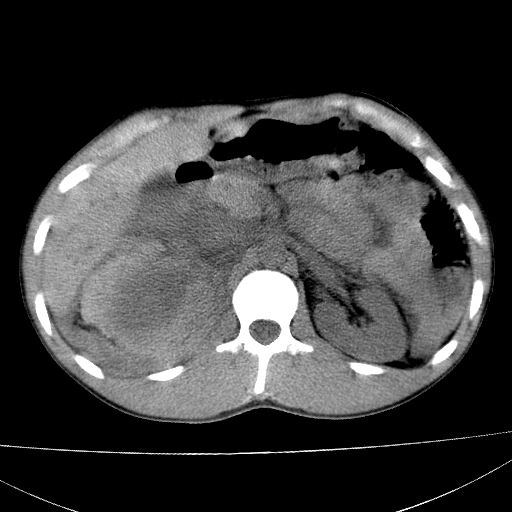

标题: CT15860:男,21岁,腹部外伤2小时伴胸疼。 [打印本页]

标题: CT15860:男,21岁,腹部外伤2小时伴胸疼。

肝脏及肾脏明显有损伤性改变并激发腹腔内积液(血),以肝脏撕裂及肾周积血显著。

1)肝破裂伴腹腔积液(血)。2)右肾破裂伴右肾包膜下及肾周血肿。3)腹部空腔脏器穿孔可能。4)右侧少量胸腔积液(血)。

肝肾挫裂伤,右肾周及包膜下血肿,腹腔积液,不排除空腔脏器穿孔,建议行增强检查

肝肾挫裂伤,右肾周及包膜下血肿,腹腔积液

肝、右肾包膜下血肿,右侧腰大肌及腹膜后血肿;腹腔少量积血;腹腔疑有少量游离气体伴肠破裂。

1肝挫伤伴腹腔积液。2右肾挫裂伤伴右肾包膜及肾后间隙肿血肿。3右肾脏周围的积气,十二指肠显示结构不清,考虑十二指肠降部破裂可能性大。